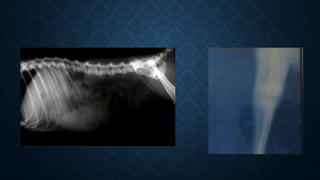

BLANK FILM/UNEXPOSED

UNEXPOSED & EXPOSED

BLANK FILM

• Causes:

a) Film not exposed.

b) Central beam not properly directed and centred on the

cassette.

• Prevention:

a) Check exposure switch and X-ray machine.

b) Ensure proper centering of the X-ray beam.

BLANK FILM • Causes: a)Film not exposed. b) Central beam not properly directed and centred on the cassette. • Prevention: a) Check exposure switch and X-ray machine. b) Ensure proper centering of the X-ray beam.